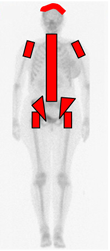

Al nacimiento la medula hematopoyética ocupa todo el esqueleto. Luego inicia la conversión a medula amarilla, de forma simétrica de la periferia al centro y de afuera hacia el centro. (Fig 1).

Fig 1. Diagrama de conversión medular.

Al nacimiento (Izquierda), casi toda la MO es roja y se convierte a MO amarilla progresivamente, de distal a proximal.